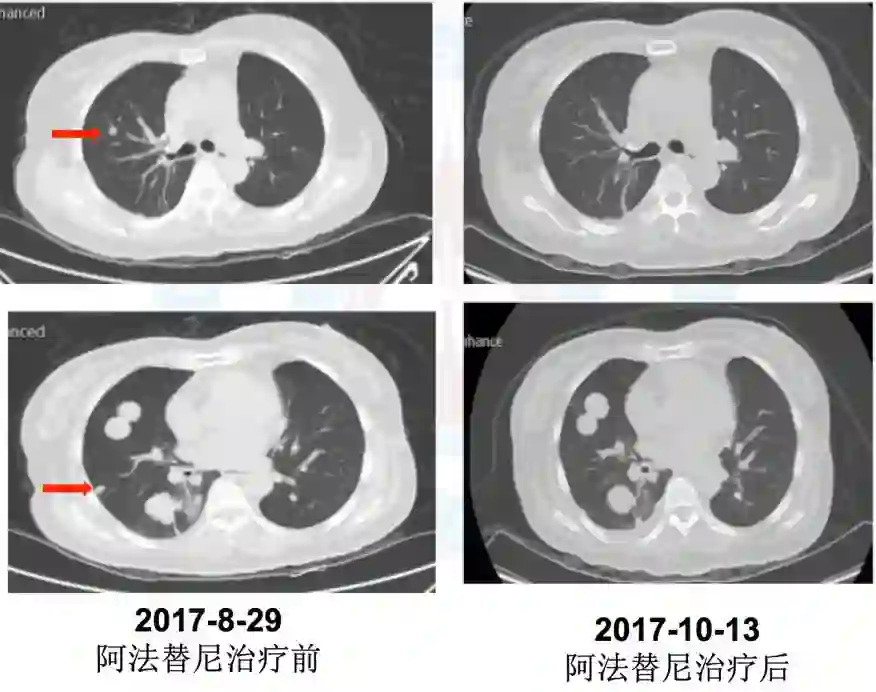

5.五线:2017年9月5日阿法替尼40mg靶向治疗,治疗1周出现I度皮疹、消化道反应,治疗45天疗效评价PD(混合疗效,部分缩小)。

肺内科李安娜医生:该患者是接受EGFR TKI治疗耐药后出现2种混合癌病理类型,这个混合癌病理类型目前考虑是肿瘤异质性引起,而不是腺癌的转化。因为最初手术切除2个肺结节病理提示是2种单纯癌组织成分,而不是混合癌成分。患者在二次肺结节穿刺活检病理提示肉瘤样癌,但给予阿法替尼治疗后部分肿瘤组织缩小,考虑缩小肿瘤组织成分为腺癌。目前患者已经是5线治疗,PS评分2分,但疼痛症状加重。既往治疗中3线治疗后,阿法替尼治疗时可以观察到部分有效。针对下一步治疗目前组内讨论意见是:因为该患者为混合性腺癌,同时存在EGFR突变,且既往阿法替尼治疗可观察到部分有效,毒副反应为轻度I度,目前已到6线治疗,无标准治疗方案,可以考虑靶向治疗联合化疗;病理为腺癌合并肉瘤样癌,可以选择泰素联合阿法替尼,间插治疗。